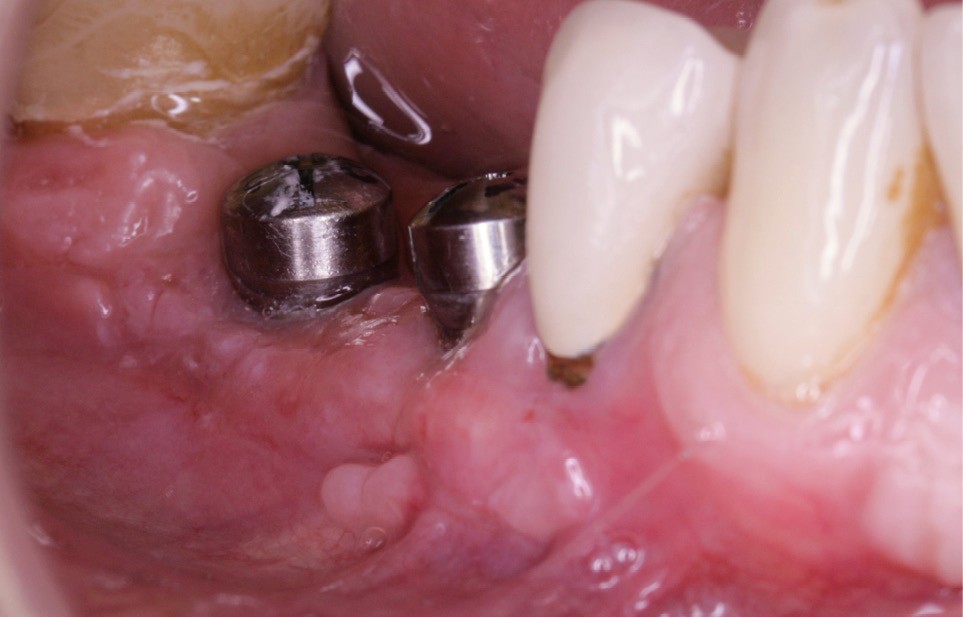

La greffe épithélio-conjonctive (GEC) [7, 8] consiste au remplacement du tissu parodontal existant par un greffon épithélio-conjonctif dont l’indication principale est l’augmentation en hauteur et en épaisseur du tissu kératinisé (fig. 2). Elle peut aussi être utilisée dans le recouvrement radiculaire (avec des résultats en termes de recouvrement inférieurs à ceux des techniques de greffe de conjonctif enfouie), l’aménagement des crêtes édentées, l’aménagement péri-implantaires [9, 10] (fig. 3), ou en association avec un traitement ortho-parodontal [11]. Le principal défaut de cette technique est son aspect inesthétique ; elle sera donc réservée à des zones non visibles comme les incisives mandibulaires ou les zones postérieures.